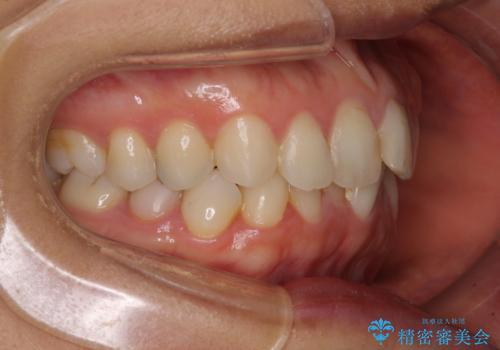

- 前歯のデコボコを気にして来院された患者様です。

IPR(歯と歯の間を削る)によってデコボコが解消するように設計し、インビザラインにより治療を行うこととしました。

下顎善の叢生をもう少し改善したかったのですが、患者様は十分に整ったとのことで治療を終えることになりました。